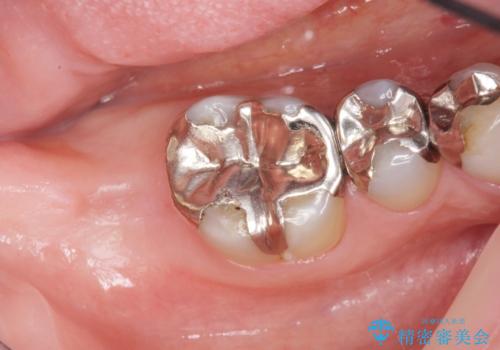

患者様のご希望によりPGA(金白金合金)クラウンによる補綴を行いました。

「金歯は咬み心地もいいし、見た目もカッコイイ!」と喜んで下さいました。

自然な使用感にご満足頂き、他の部位もPGAクラウンによる治療をご希望され現在治療中です。

クラウンの種類:PGA(Platinum Gold cast Alloy・金白金合金)クラウン